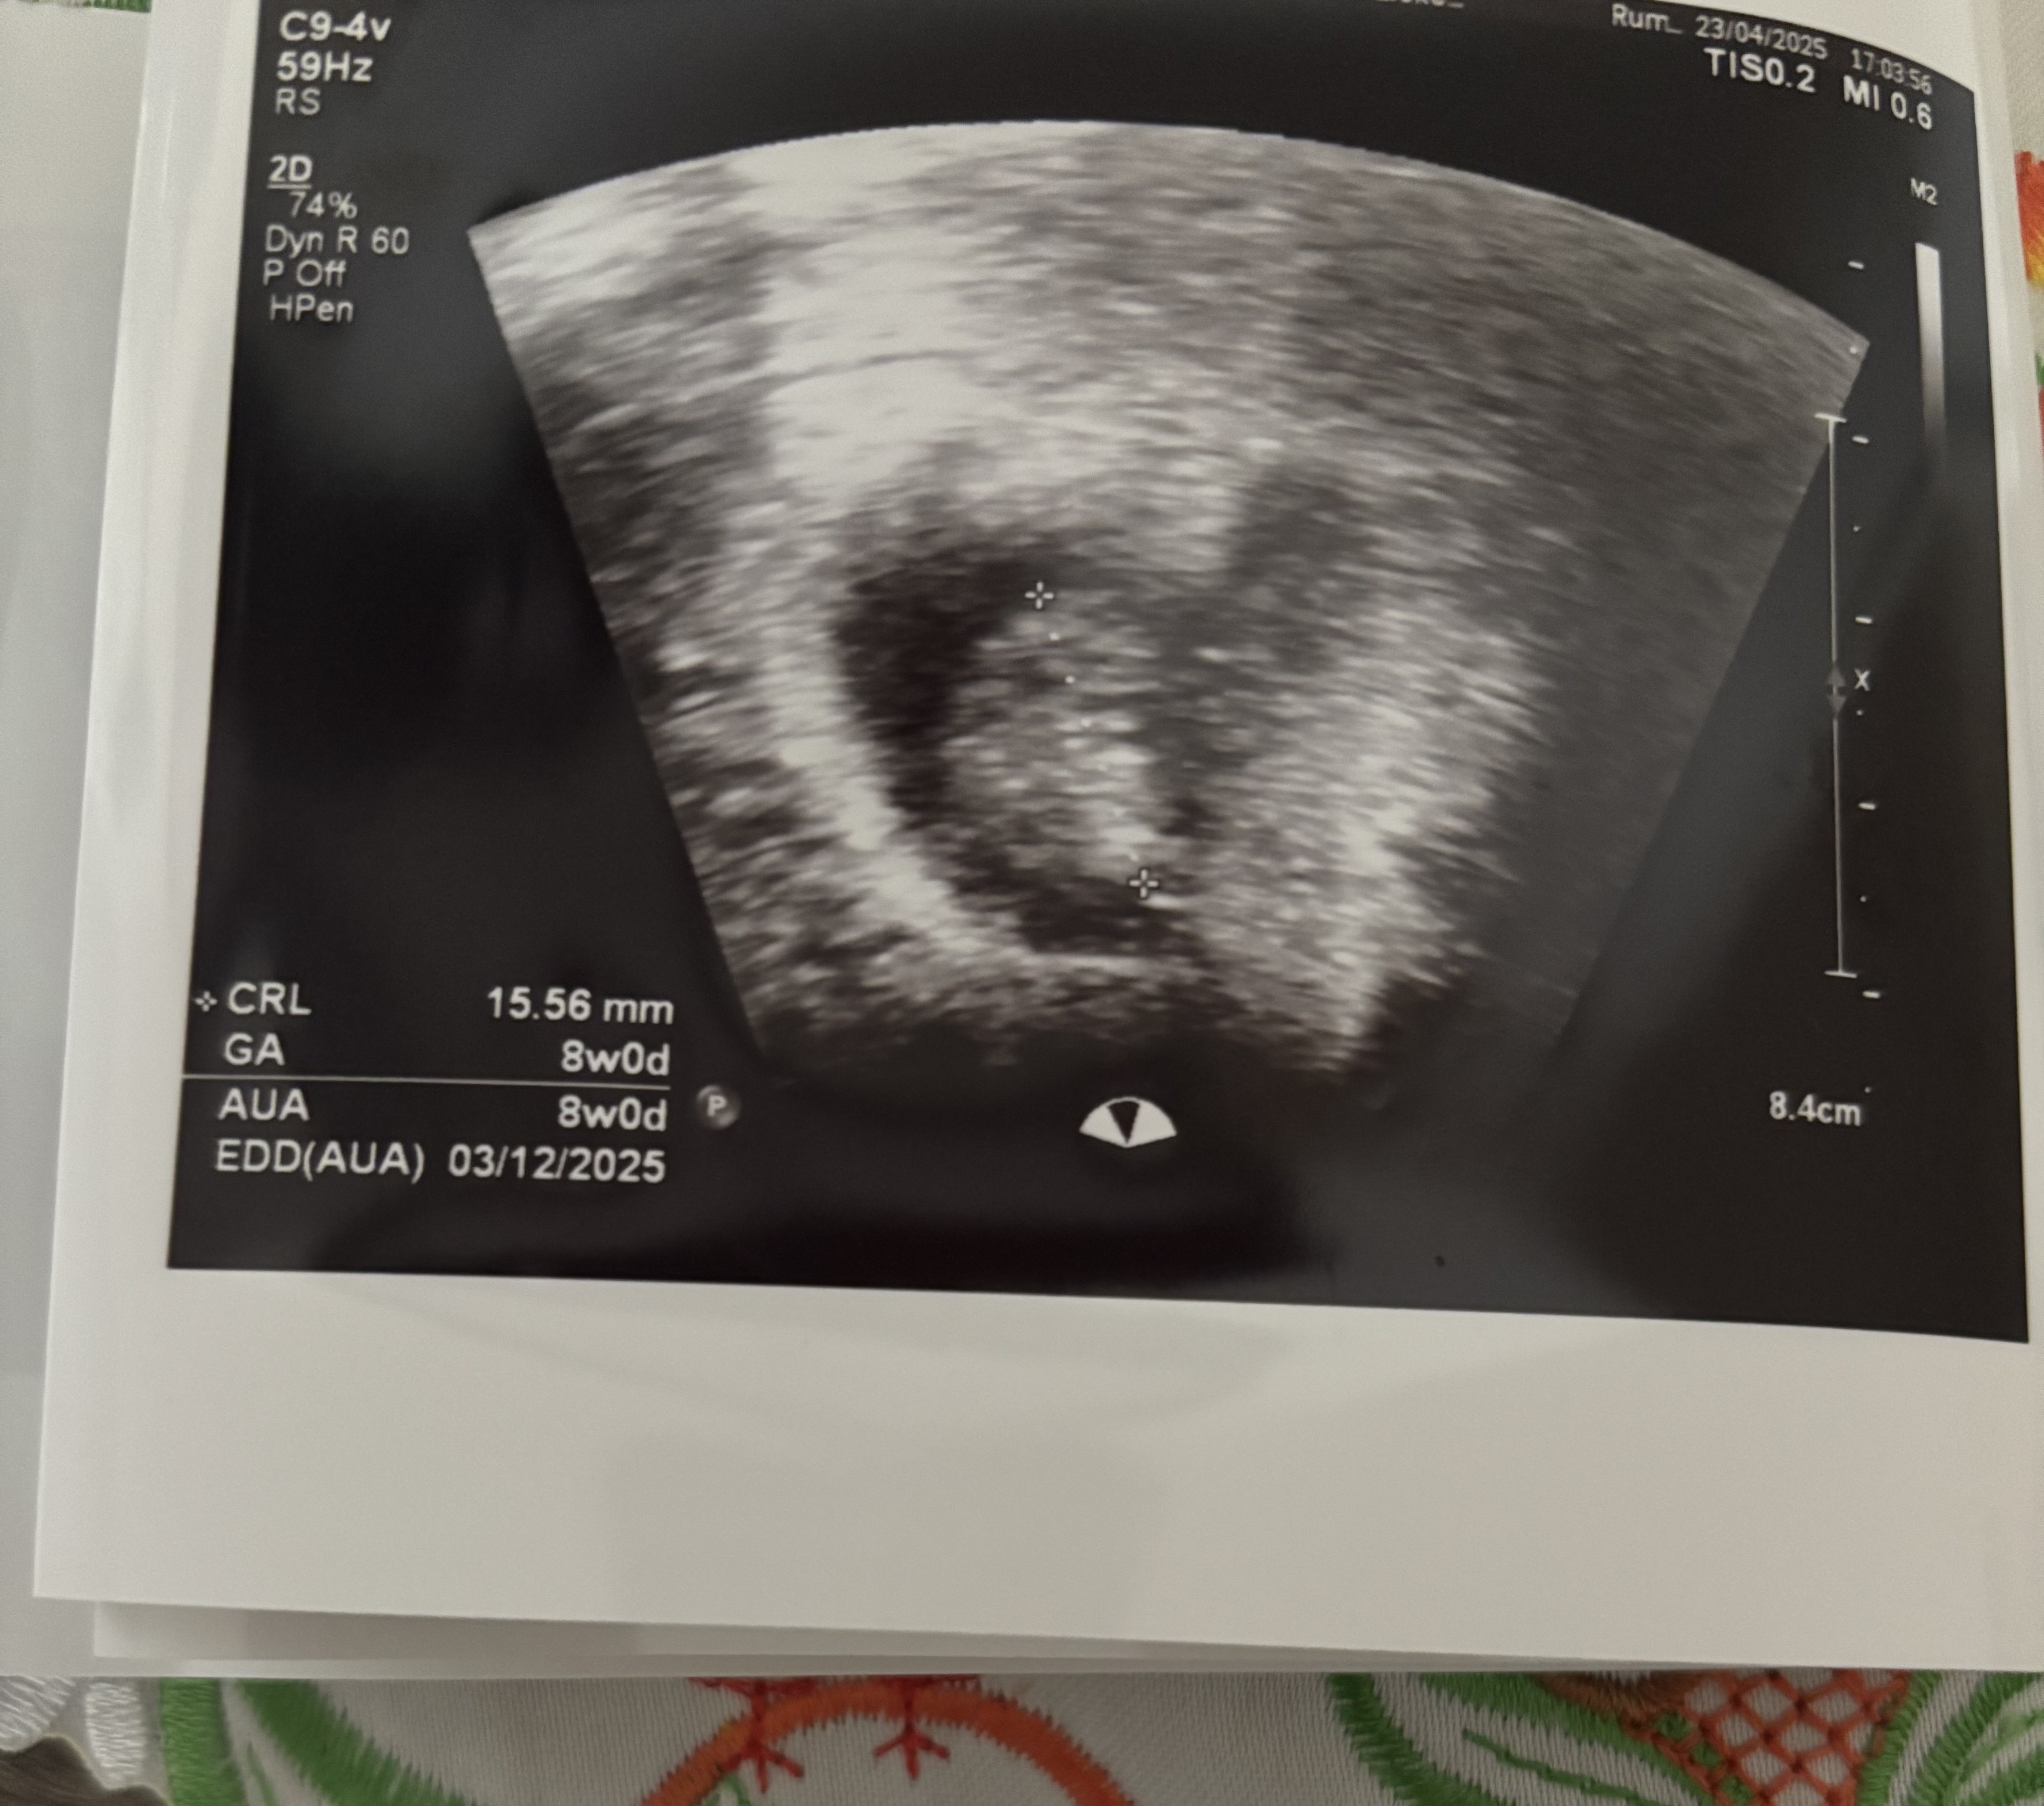

Dziewczyny z opóźnieniem ale mamy to ♥️ 1,5cm człowieczka, moja okruszynka. Wszystko się zgadza z wyliczeniami moimi 🥰🥰🥰 ale mi serce wali. Kolejne USG za 2tyg.

Załączniki

• IMG_3072.jpeg

IMG_3072.jpeg

1,9 MB · Wyświetleń: 82